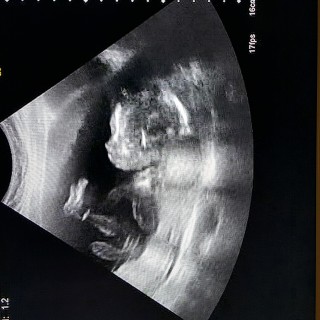

写真:19w2d:かじさん:ファイティングポーズ

19w2d!4週間ぶりのエコー!!

久しぶりなのに淡々と説明され性別も、確定ならず(><)

頭は週数通りで元気だと言われました。次の検診で性別わかるといいな〜。